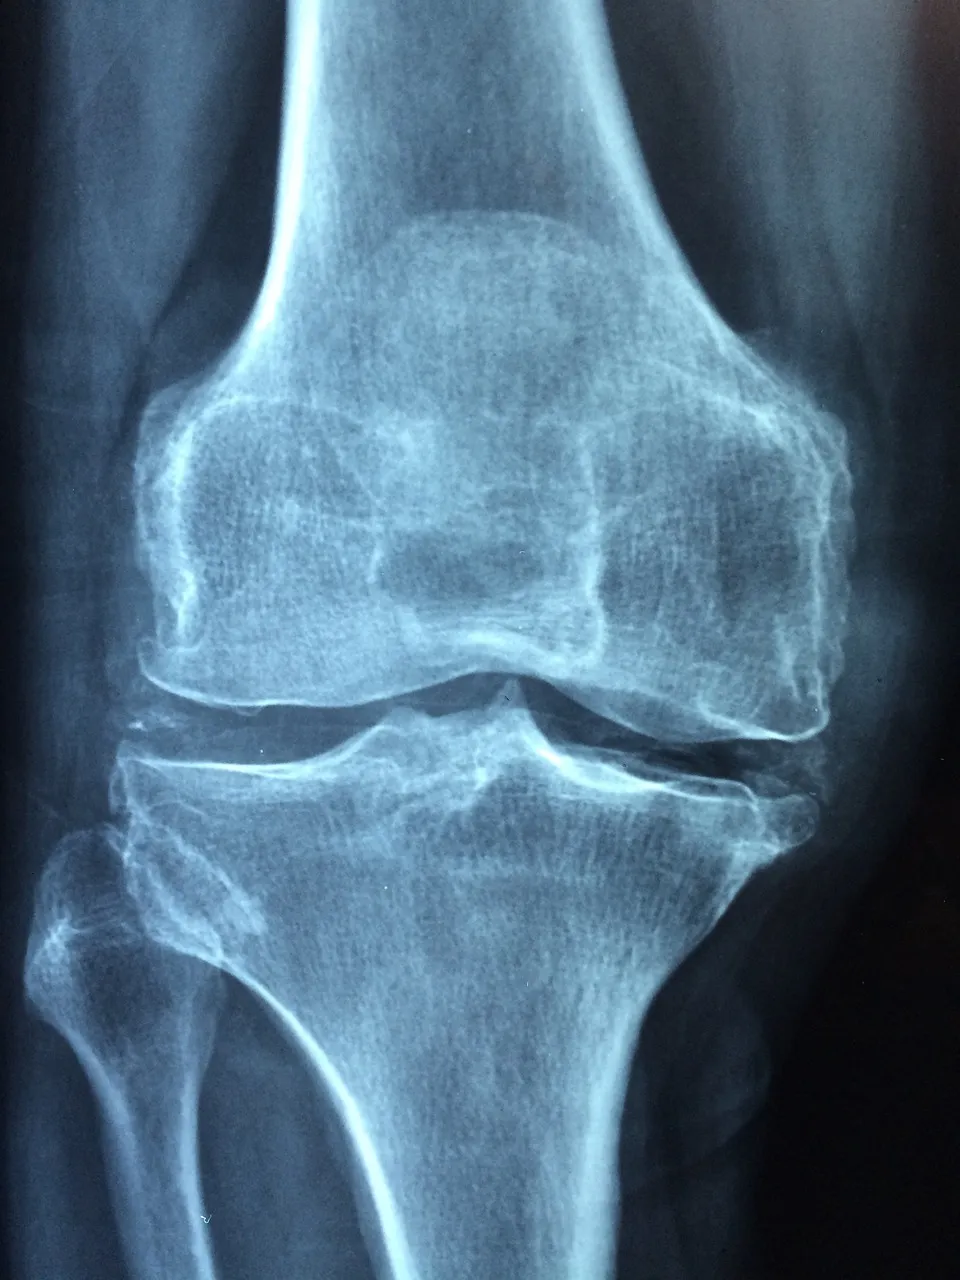

Osteoarthritis

Evidence shows that PEMF moves the cells back into homeostasis, reduces inflammation, and promotes bone growth to reverse osteoarthritis.

“That machine is absolutely amazing. I went into spring training last year with a little bit of inflammation in my knee. I put the QRS machine on it and immediately the swelling was gone. I was like, ‘Wait a minute. That’s really wild.’ I remember a couple times last year where I got hit and Grady (Little) took me out of the game. I told the trainer, ‘No offense to what you guys are doing, but I’ve got a hyperbaric chamber at home and I’ve got a QRS machine. Do you want me to get out of here so I can be in the game tomorrow?”